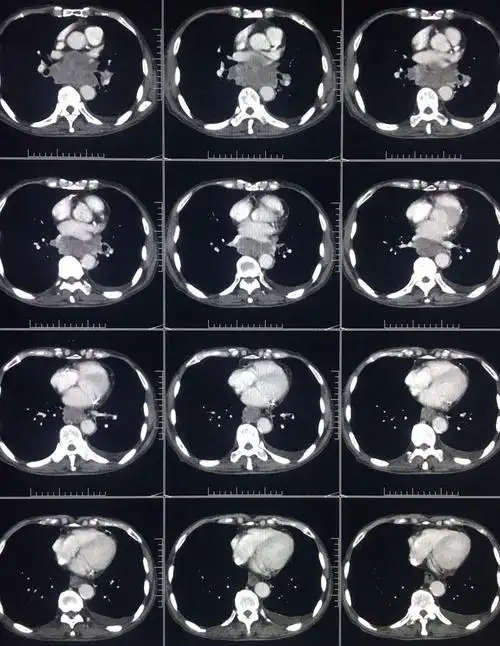

胸部ct平扫

图片是患者ct平扫和多期增强扫描(动脉期,静脉期,平衡期或延迟期)的

胸部ct平扫示左下肺占位肺癌

ct平扫 三期增强,这个纵隔占位有点难 [病例帖]